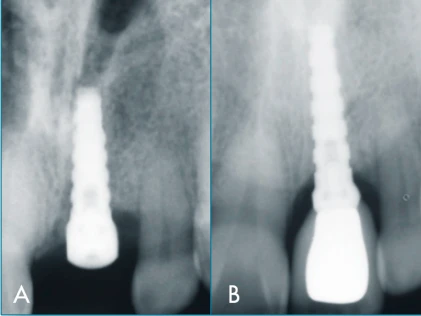

Implant Body Shape

tapered

Implant Body Features

non-threaded

Implant Cervical Shape

wider than body

Implant Cervical Features

polished surface

Implant Apical Features

grooved, notch

Implant Apical Shape

flat apex

Implant Body Surface

acid etching

Implant Apical Feature: Grooves and Apical Notch.

Platform to Abutment Connection: Parabolic Platform. 2.5mmx4.9mmx3.75mm.